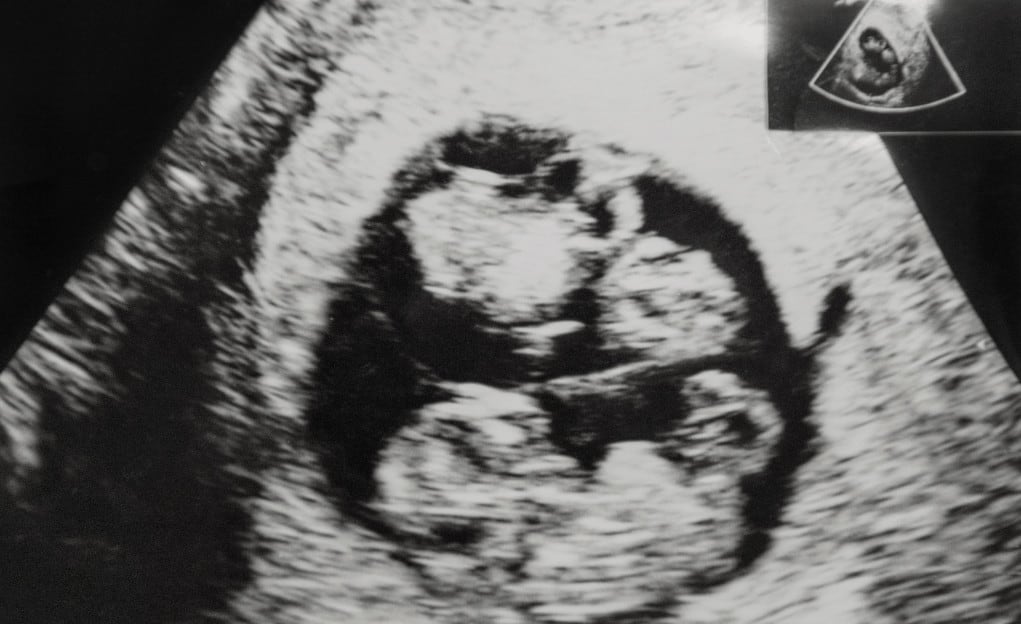

Maar opnieuw komt het terug. Het knagende, lege eenzame gevoel komt weer naar boven. Nog meer naar binnen en ‘kijken’ en ‘voelen’ of er een herinnering aanwezig is. En jawel, tijdens een afstemming komt er een beeld in haar geheugen naar boven. Een tweeling, als ieniemienie foetussen van ongeveer 9 weken oud, aanwezig in de baarmoeder met als beeld zichzelf en haar andere helft. Wauw! Blij en verwonderd, maar helaas dat is van korte duur.